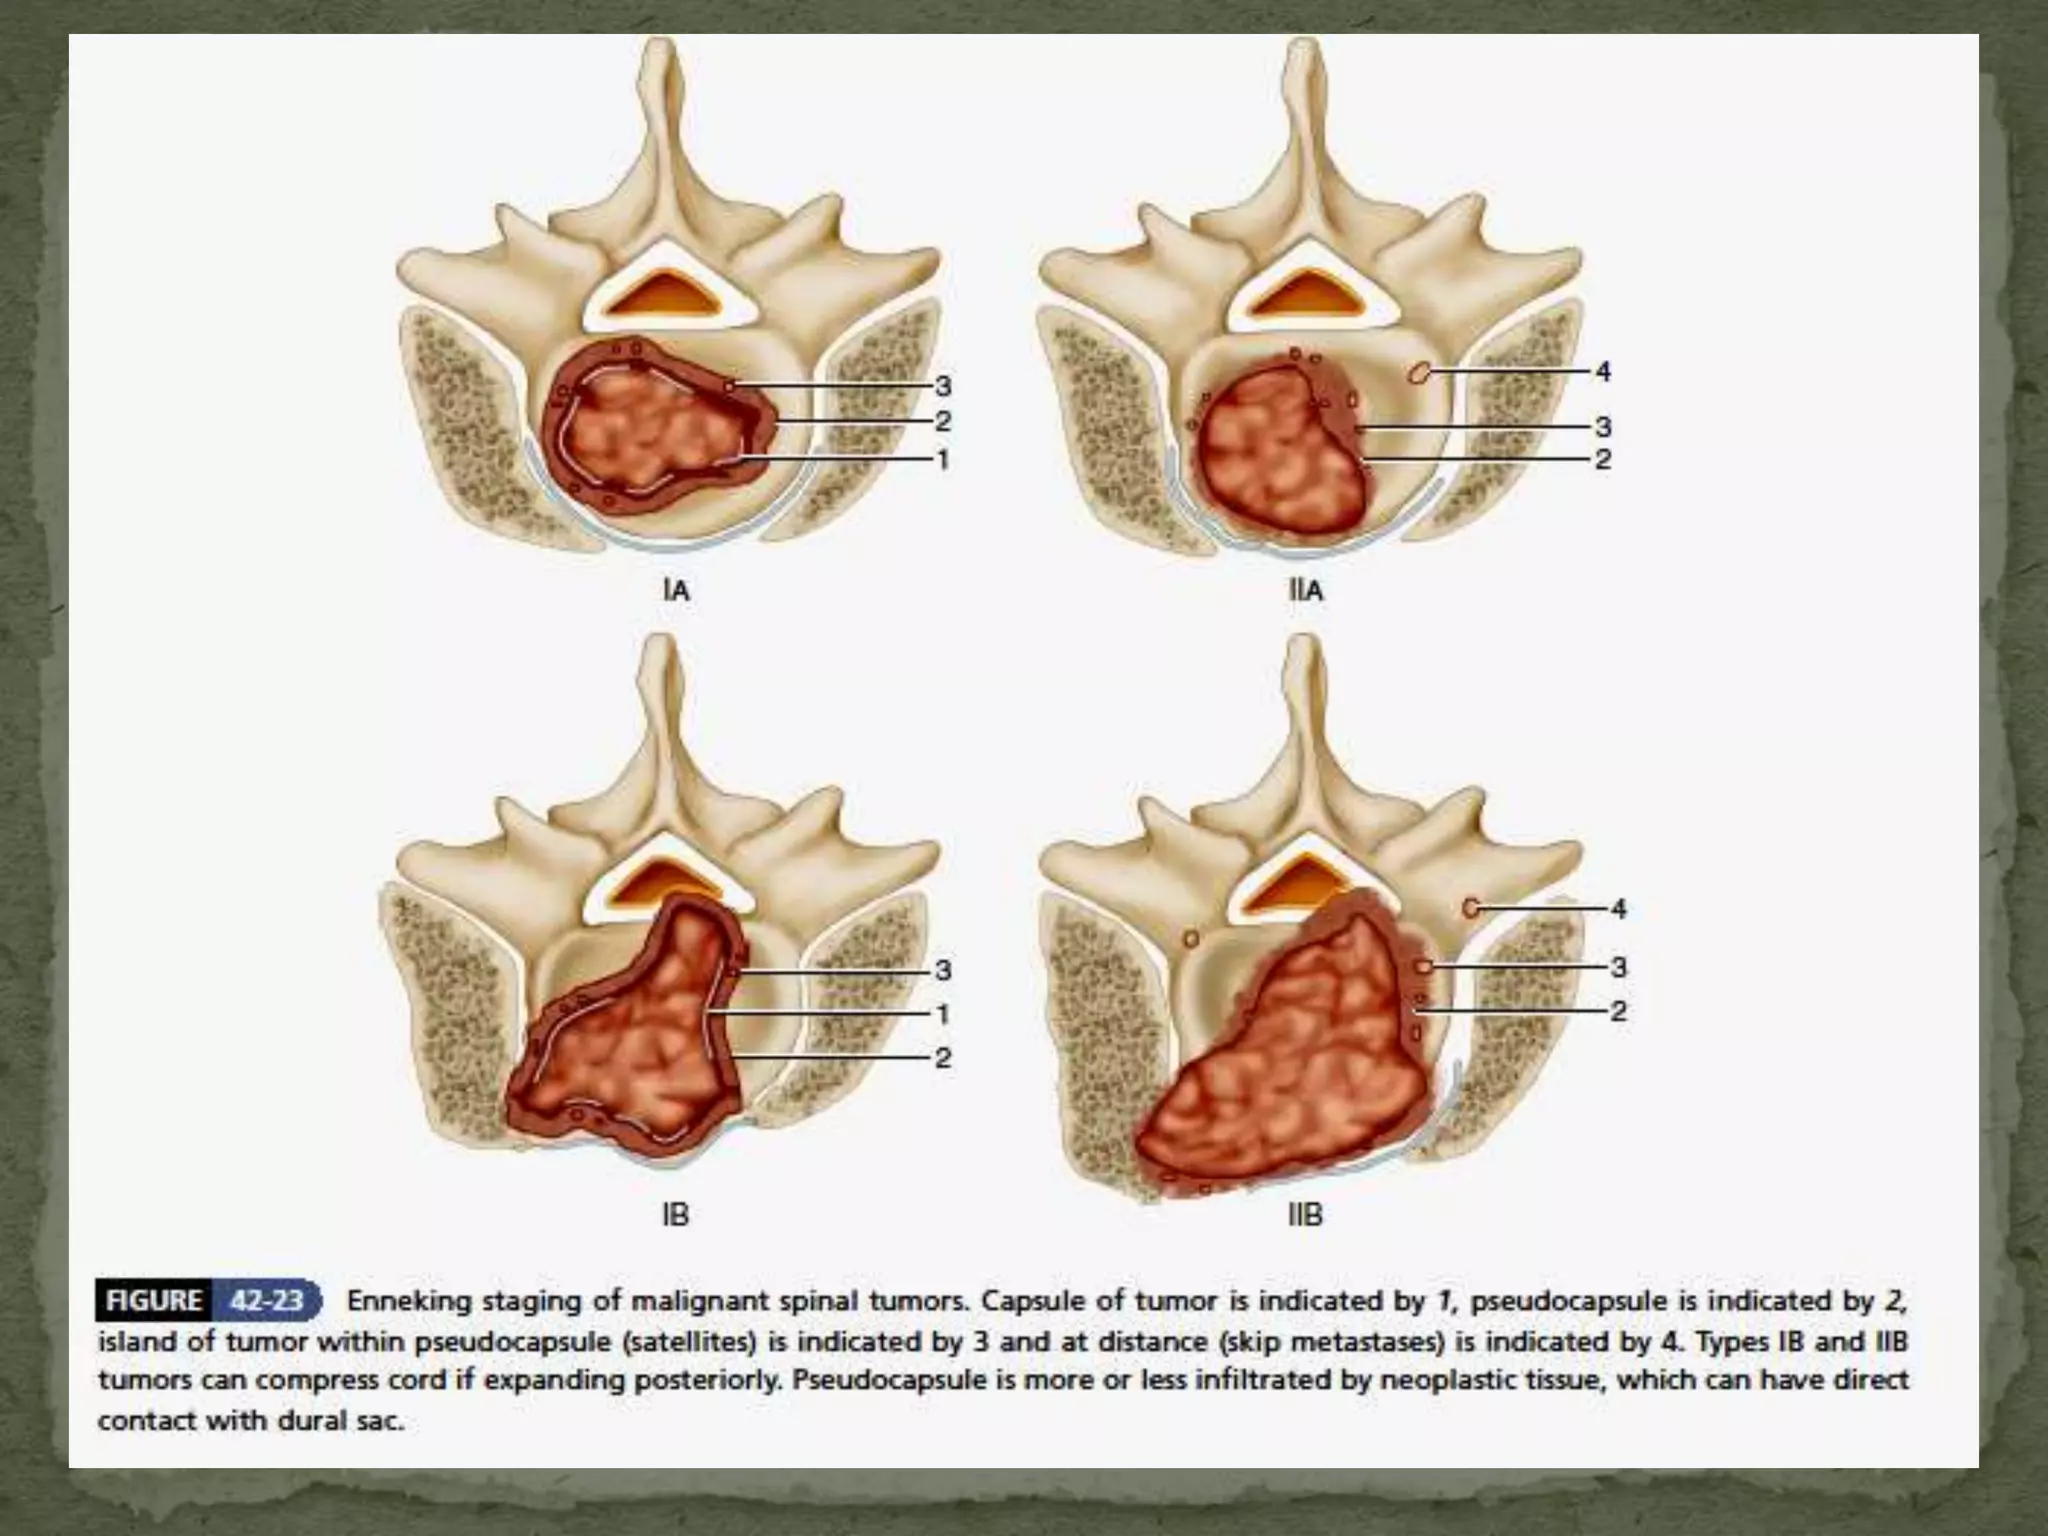

The surgical techniques are classified by the tissue planes

and approach as:

 curettage

 intralesional resection

 en bloc resection